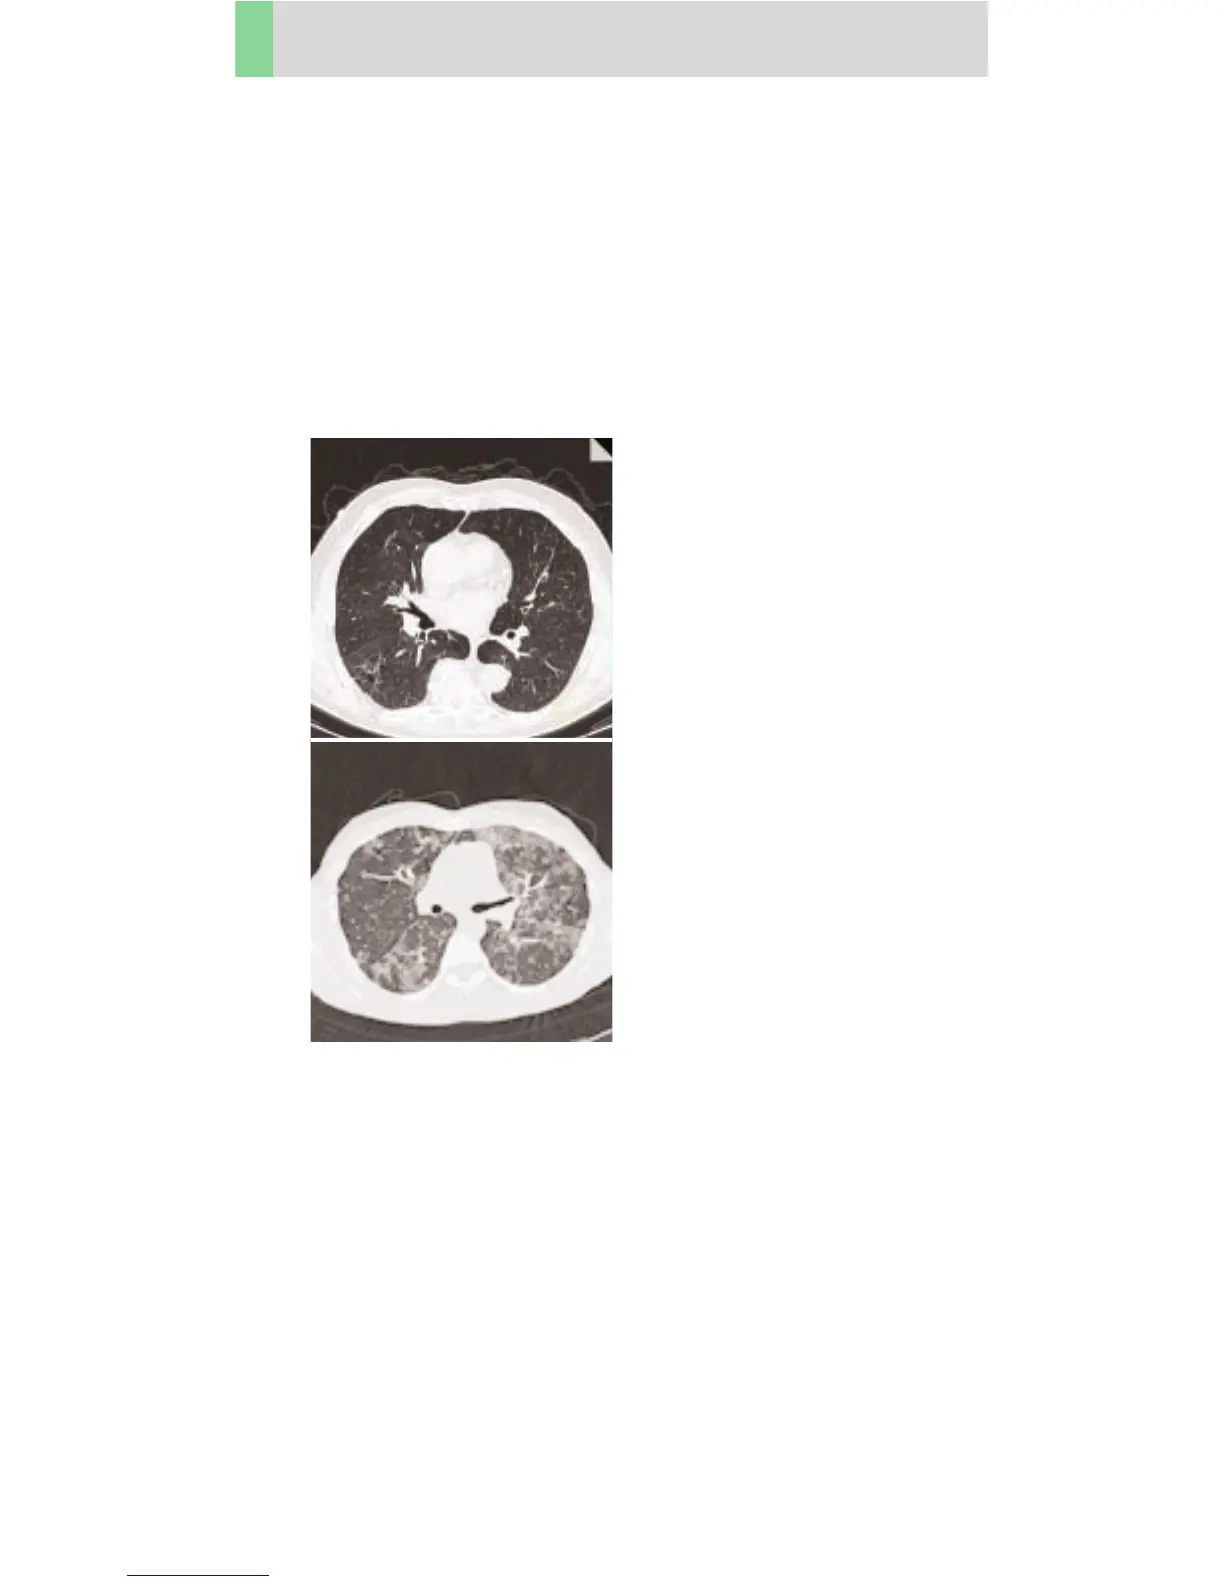

Thorax

ThoraxSeqHR

Indications:

Sequence mode for HiRes lung studies. E. g. interstitial

changes in the lungs.

Images are acquired in 10 mm intervals.